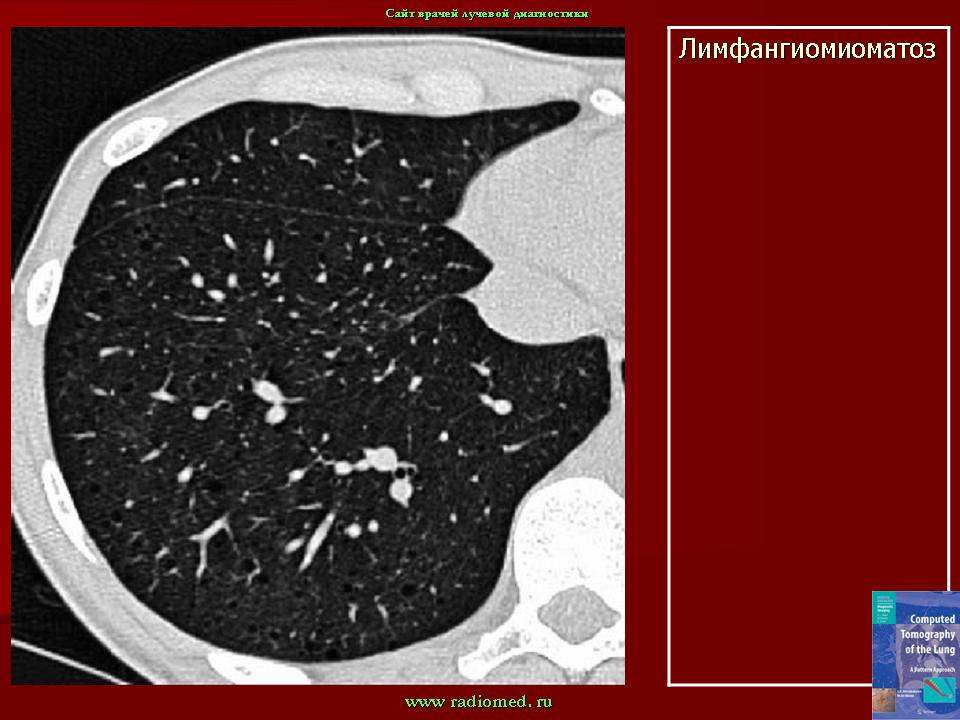

лимфангиолейомиоматоз

Типичный пример патологии при которой основным патерном являются кисты - :

материал взят со статьи Dr.Mario

http://www.radiomed.ru/publications/luchevaya-diagnostika-diffuznykh-interstitsialnykh-zabolevanii-legkikh-dizl-obshchie--0

Лимфангиомиоматоз.

Из архива AFIP. Лимфангиолейомиоматоз.

Лимфангиолейомиоматоз.